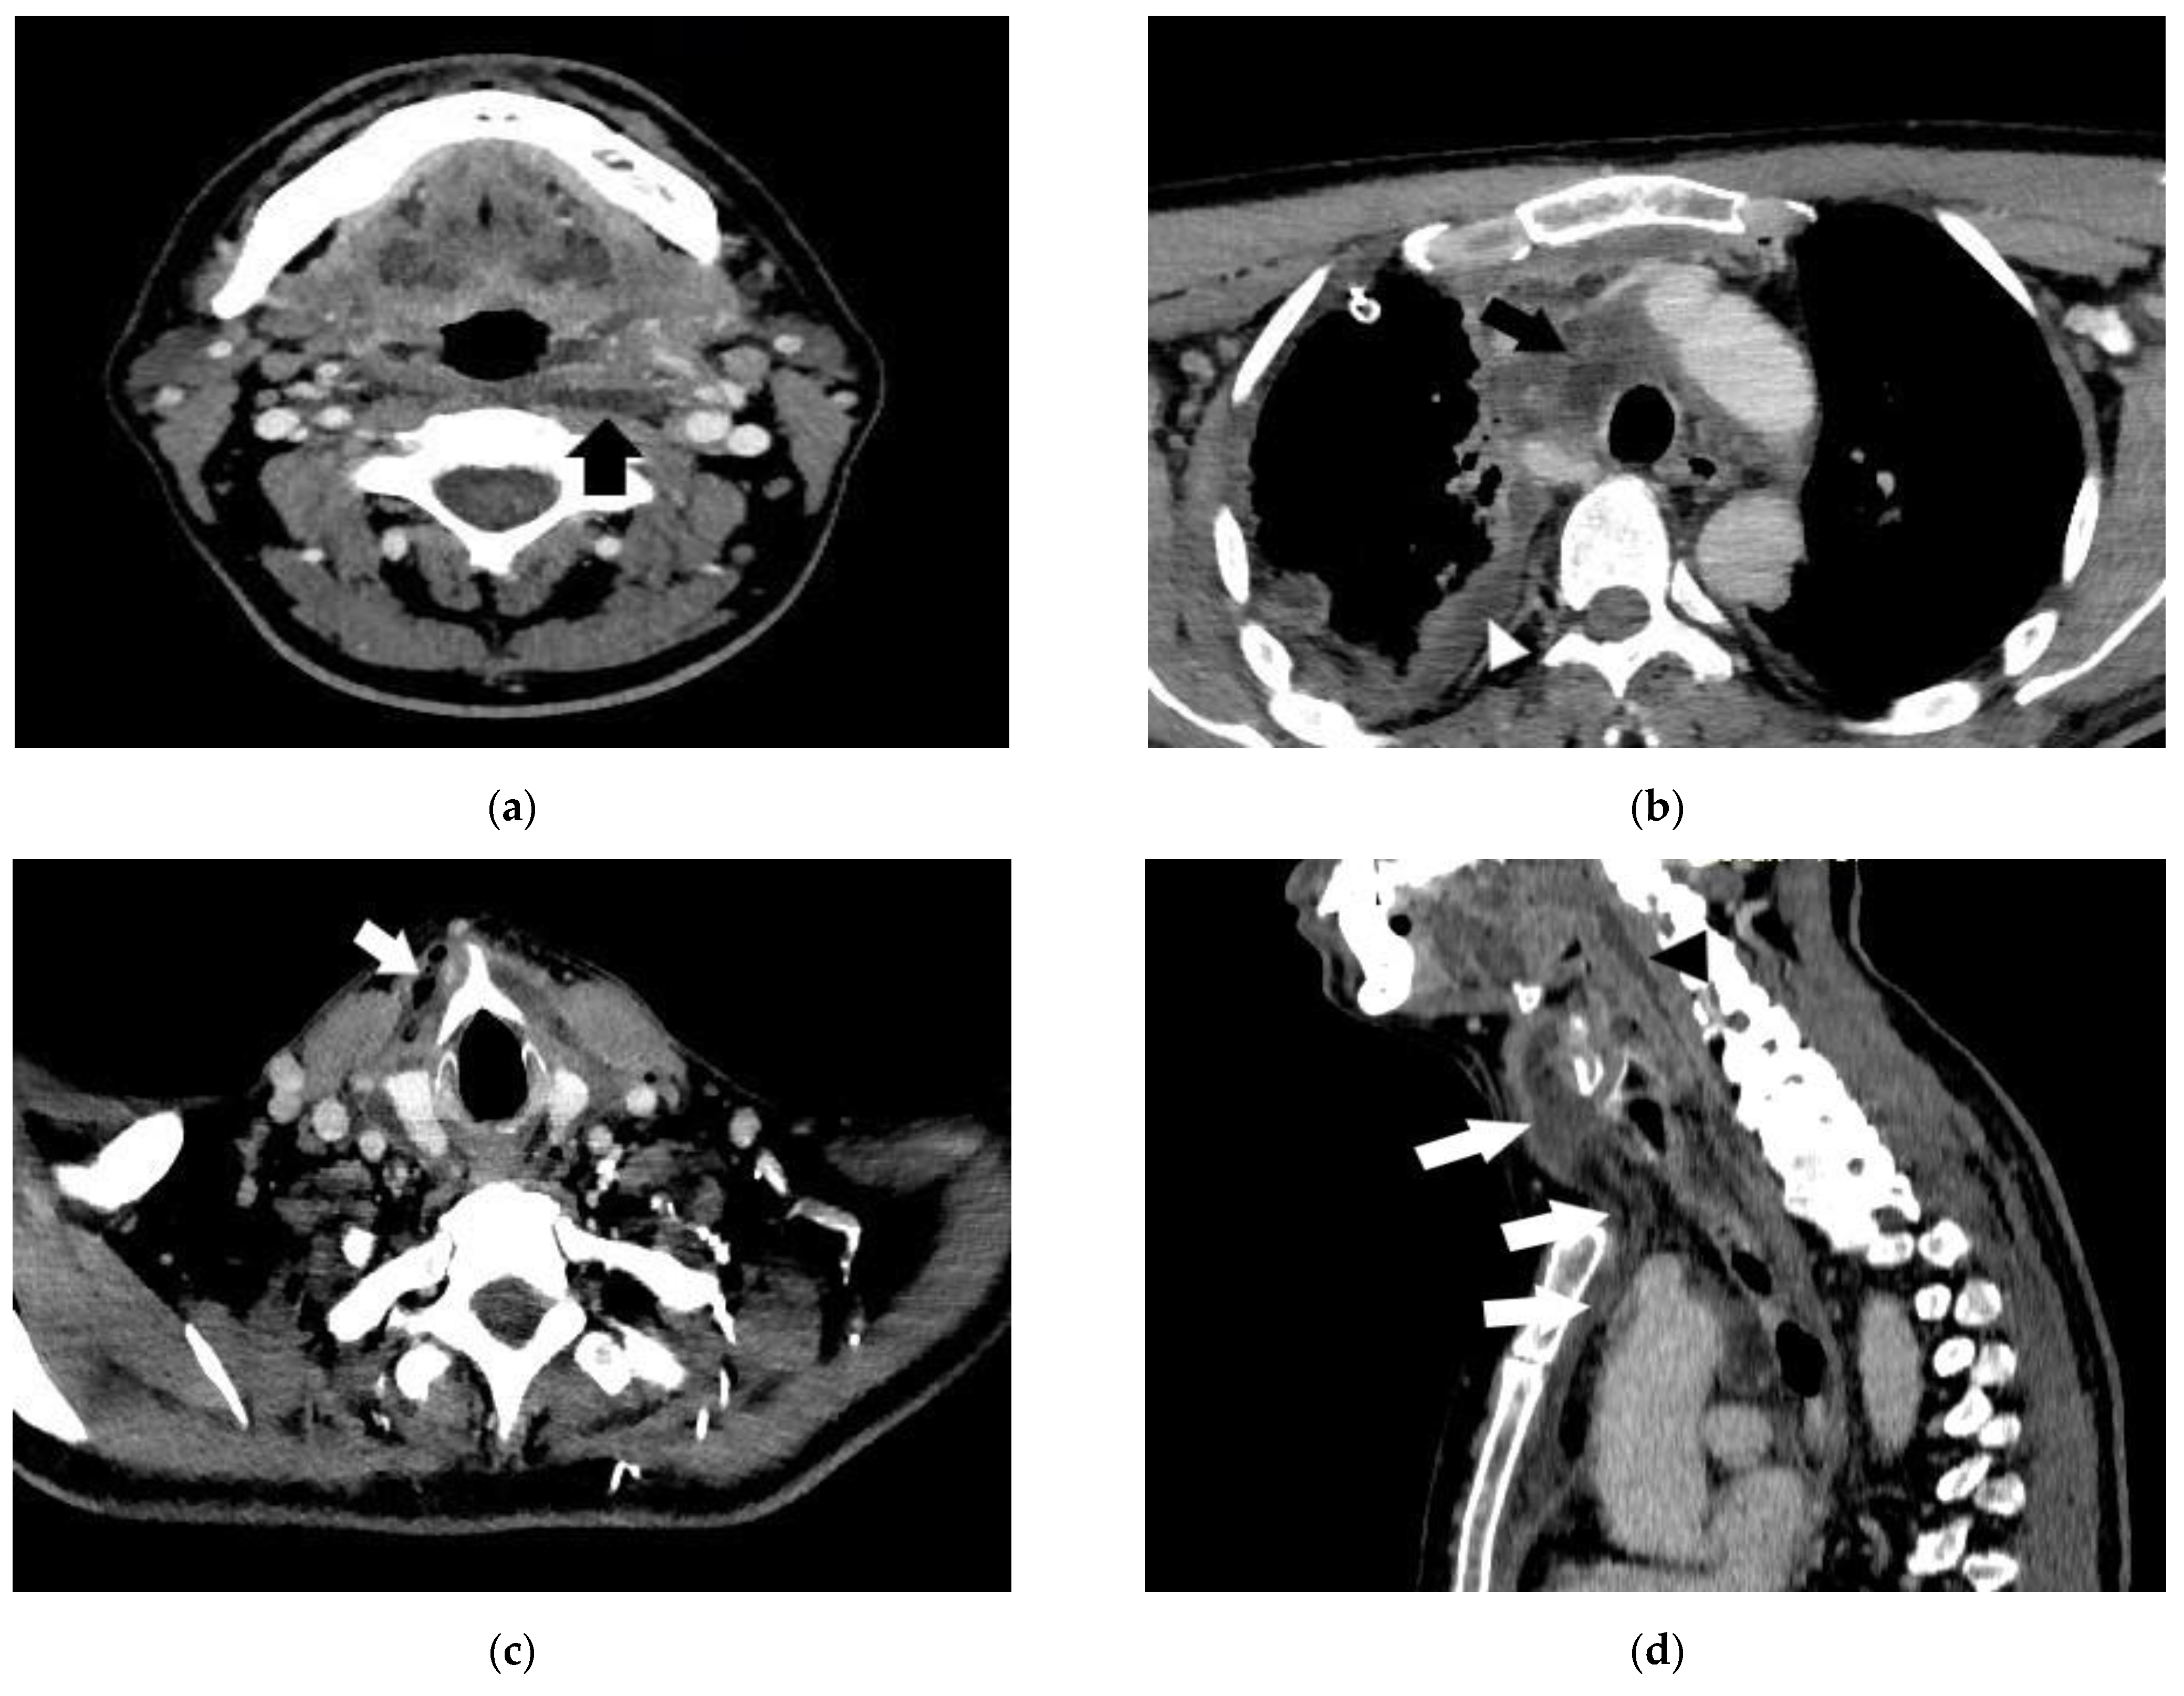

- Case 1.

- Case 2.

- Case 3.

- Case 4.